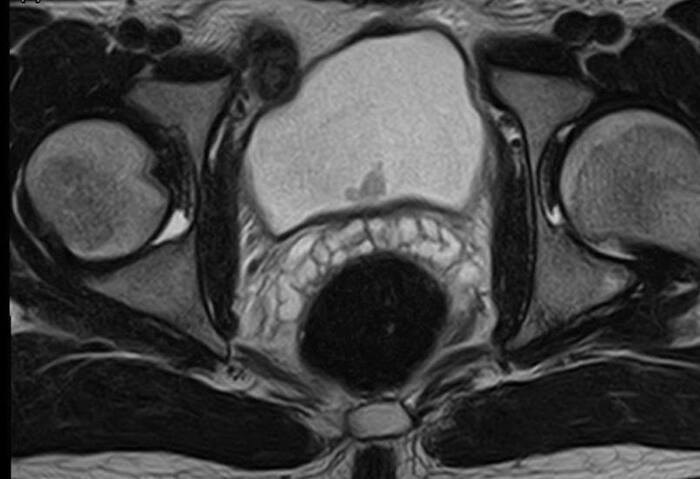

Склероз шейки мочевого пузыря после трансуретральной резекции предстательной железы. Хирургическое лечение

М, 78

Жалобы: невозможность самостоятельного мочеиспускания.

Анамнез: 2018 г.  - ТУР предстательной железы. С 2023г. отмечает затрудненное мочеиспускание. 08.2025 г. - острая задержка мочи, выполнена троакарная цистостомия.

На ретроградной уретрографии визуализируется критическое сужение в области шейки мочевого пузыря.

Диагноз: ДГПЖ. Трансуретральная резекция предстательной железы от 2018г. Склероз шейки мочевого пузыря. Цистостома. Конкременты мочевого пузыря.

Выполнено: Трансуретральная лазерная инцизия шейки мочевого пузыря. Цистолитотрипсия.